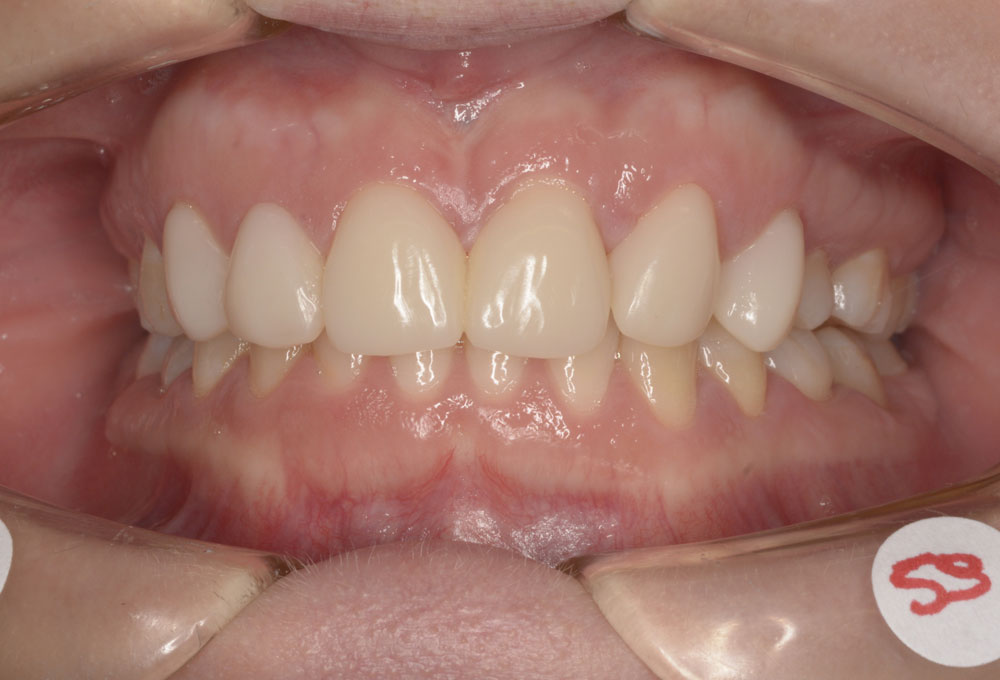

In questa terapia ortodontica si procede con il recupero dello spazio che sarebbe stato a disposizione dell’elemento del dente agenesico, al fine di una successiva sostituzione protesica dei denti mancanti.

La riapertura degli spazi viene eseguita per perfezionare le posizioni dentali e favorire la successiva riabilitazione protesica.

In questo caso, l’Ortodontista richiede la preventiva valutazione riabilitativa protesica al collega dentista, che fornirà le informazioni necessarie in merito alle future esigenze di spazio e posizione dentale per una miglior esecuzione del lavoro protesico previsto.